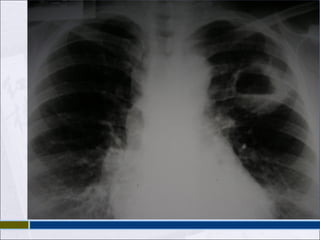

 PAR RADIOLOGICOY PROY. LORDOTICA  MÁS FRECUENTE INFILTRADO EN SEGM APICALES DE LÓB SUP Y EN SEGM SUPERIORES DE LÓBULOS INF.  PUEDE APARECER CAVITACIÓN.

 BRONCÓGENA SEVE IMAGEN MÁS EXTENSA, CON PATRÓN DESTRUCTIVO.  HEMATÓGENA: PATRÓN MILIAR: PEQUEÑOS NÓDULOS DE UNOS 2 MM, REPARTIDOS DE FORMA DIFUSA Y HOMOGÉNEA POR AMBOS CAMPOS PULMONARES.

 DEPENDE DELGRADO DE INMUNODEPRESION  DESDE NORMAL HASTA EXTENSOS INFILTRADOS BILATERALES  NO RESPETA LOCALIZACIONES TIPICAS  50% TIENEN ADENOPATIAS INTRATORACICAS  TBC ES LA PRINCIPAL CAUSA DE DERRAME PLEURAL EN HIV.  ES RARA LA CAVITACION.  Rx EMPEORA TRANSITORIAMENTE LUEGO DE 1-5 SEMANAS DE INICIADO EL HAART

• #37 Radiografía de tórax En la primoinfección tuberculosa, es típica la aparición de un infiltrado en las regiones medias del pulmón, por ser éstas las mejor ventiladas. Es posible ver un ensanchamiento hiliar y mediastínico por agrandamiento de los ganglios. Las lesiones primarias curadas pueden dejar un nódulo periférico calcificado, que, junto con un ganglio hiliar calcificado es lo que se conoce clásicamente como Complejo de Ghon. En la tuberculosis de reactivación, la imagen radiológica más frecuente es la aparición de un infiltrado en los segmentos apicales de los lóbulos superiores, y en los segmentos superiores de los lóbulos inferiores. Además del infiltrado, puede aparecer cavitación. A veces, la imagen es más clara en una proyección lordótica, que facilita la visión de imágenes que pueden estar ocultas por la confluencia de las primeras costillas y la clavícula. Cuando existe diseminación broncógena, se puede observar un imagen más extensa, con patrón destructivo. En la diseminación hematógena es característica la afectación pulmonar, cuya imagen en la radiografía de tórax se denomina patrón miliar (por la similitud con las semillas de mijo). Este patrón se caracteriza por la imagen de pequeños nódulos de unos 2 mm, repartidos de forma difusa y homogénea por ambos campos pulmonares. Es mejor observada en la radiografía lateral. Términos como &amp;quot;lesiones fibróticas&amp;quot;, &amp;quot;cicatriciales&amp;quot;, &amp;quot;inactivas&amp;quot;, se deberían evitar en la evaluación de una sola radiografía de tórax, pues la inactividad de una tuberculosis pulmonar no se puede afirmar por una imagen aislada. Sin embargo, aquellas imágenes que no cambian en radiografías seriadas durante 3 ó 4 meses si son más sugestivas de una tuberculosis antigua (o de otro proceso). Es frecuente ver en estas lesiones antiguas retracciones del hilio pulmonar o desviación de la tráquea. Dicho esto, hay que saber que la tuberculosis se puede manifestar radiológicamente con cualquier tipo de imagen, incluso con radiografía normal. En un estudio publicado en la revista Chest en el año 1999, los enfermos con radiografía normal y cultivo positivo suponían el 4,8 por ciento del total de los 518 pacientes con cultivo de esputo positivo de su serie (todos tenían clínica: tos de más de un mes de evolución, fiebre de más de una semana, o habían tenido una conversión del PPD en los dos últimos años). La presentación radiológica en el VIH difiere de la del inmunocompetente, de forma que cuanto más inmunodeprimido esté el enfermo, más probable es que la imagen difiera de la típica ya comentada. Esta presentación radiológica es muy variable, desde la radiografía normal (más frecuente que en el inmunocompetente, del 5 al 10 por ciento de los casos con cultivo positivo según las series), hasta extensos infiltrados pulmonares bilaterales que confundan el cuadro con una neumonía por P. carinii. Suelen estar ausentes los signos clásicos de cavitación, que sólo aparecen en un 10 por ciento de los casos, siendo menos frecuente cuanto mayor sea el grado de inmunosupresión. Es de destacar la alta frecuencia de adenopatías intratorácicas, que se presentan en el 50 por ciento de los paciente con tuberculosis pulmonar. No es raro el derrame pleural, de presentación clínica similar a los inmunocompetentes. Como en éstos, la tuberculosis sigue siendo la principal causa de derrame pleural en los pacientes VIH positivos, aunque otras infecciones (criptococosis, neumonías bacterianas, endocarditis derecha en pacientes usuarios de drogas intravenosas) y tumores (sarcoma de Kaposi, linfoma no Hodgkin), pueden causarlo con frecuencia. Debe recordarse, además, que en nuestro medio la tuberculosis pulmonar es una de las complicaciones que con mayor frecuencia se asocia al desarrollo de neumotórax espontáneo, y que debe considerarse en le diagnóstico diferencial, junto con la neumonía por P. carinii (especialmente recibe pentamidina en aerosol como profilaxis) y las neumonías bacterianas. La afectación parenquimatosa por tuberculosis puede originar cualquier tipo de infiltrado radiológico. No existe predilección por ninguna localización ni patrón específicos, o por la extensión de la afectación. La tuberculosis no debe ser excluida ni confirmada por el aspecto del infiltrado radiológico, y en este sentido es una de las grandes simuladoras. Sólo el patrón miliar tiene una alta especificidad en el diagnóstico de tuberculosis. Un fenómeno digno de ser mencionado en los enfermos VIH-positivos con tuberculosis es el empeoramiento transitorio que se puede producir en la imagen radiológica tras el inicio del tratamiento antirretroviral. Este empeoramiento se puede manifestar como aumento de infiltrados previos, aparición de adenopatías o derrame pleural. También pueden aparecer lesiones en zonas radiológicamente normales en placas previas. Puede acompañarse de fiebre. Suele ocurrir entre 1 y 5 semanas tras el inicio del tratamiento antirretroviral. Estos episodios son similares en su presentación a las ya descritas desde hace mucho tiempo, pero mucho menos frecuentes, respuestas paradógicas que pueden aparecer tras el inicio del tratamiento tuberculostático. El fenómeno puede ser el resultado de la recuperación del sistema inmunológico, como sugiere el hecho de que se recupera la reacción de hipersensibilidad a la tuberculina en pacientes que previamente eran anérgicos. Tras excluir otras infecciones concomitantes, el tratamiento antirretroviral se debe mantener, y considerar la utilización de corticoides para el control de los síntomas.